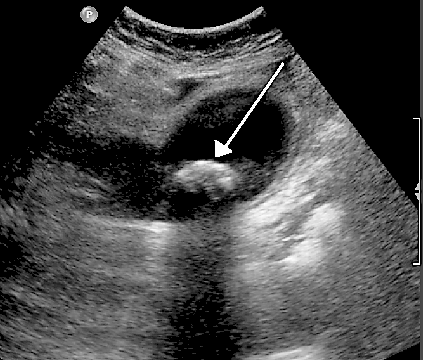

Another example is that when ultrasound travels though bile in a gallbladder it will echo back strongly if it hits a solid gallstone - as in the ultrasound image below. The arrow points to a gallstone in the gallbladder.

Gallstone ultrasound image

© By James Heilman (Own work), via Wikimedia Commons